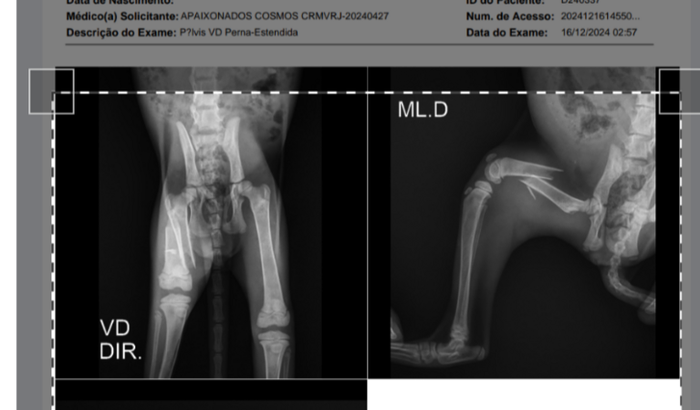

Ao levar na veterinária e fazer alguns exames, descobrimos que ela tem uma séria fratura que precisa de cirurgia urgente.